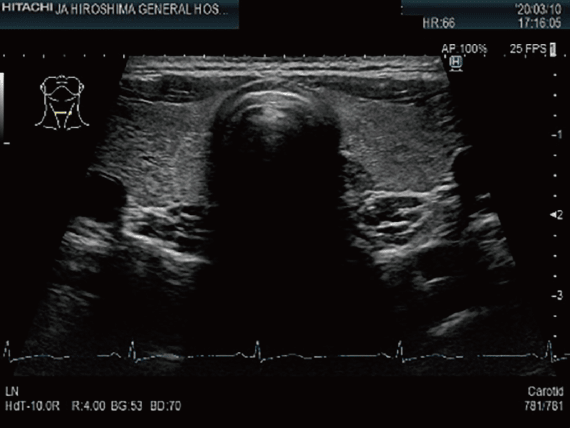

甲状腺超音波検査

頸部より超音波を照射して,甲状腺を観察する検査です。甲状腺の大きさや腫瘍の大きさ・性状・位置などの評価に用いられます。